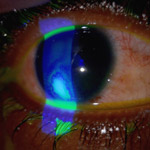

Central Serous Chorioretinopathy

A small break that forms in the pigment layer of the retina.